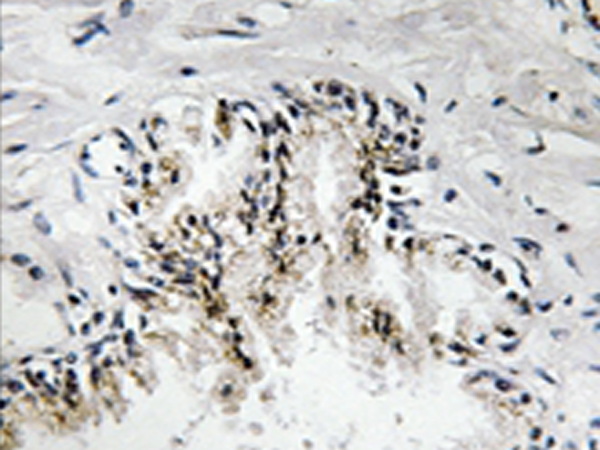

IHC |

IHC positive control: |

Human prostate tissue |

IHC Recommend dilution: |

50-100 |